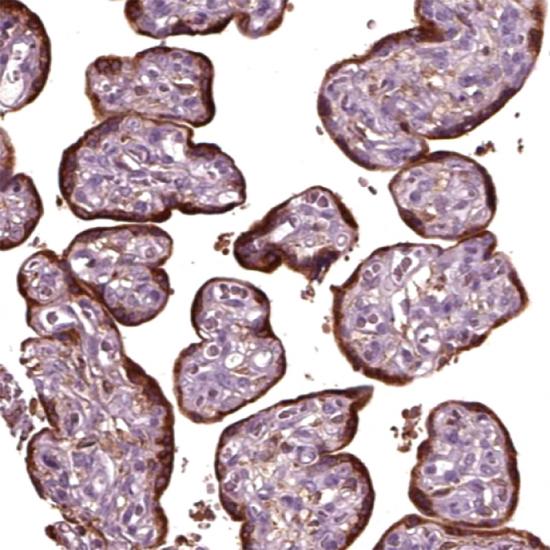

鼠抗人人糖蛋白激素α亞基(hCG-α)單克隆抗體

• 預(yù)處理:

熱修復(fù)

• 陽性部位:

細(xì)胞漿

• 陽性對(duì)照:

胎盤

人絨毛膜促性腺激素(HCG)是由胎盤的滋養(yǎng)層細(xì)胞分泌的一種糖蛋白,它是由α和β二聚體的糖蛋白組成。HCG-α在許多惡性腫瘤中存在表達(dá),可能與腫瘤的發(fā)生發(fā)展有關(guān)。